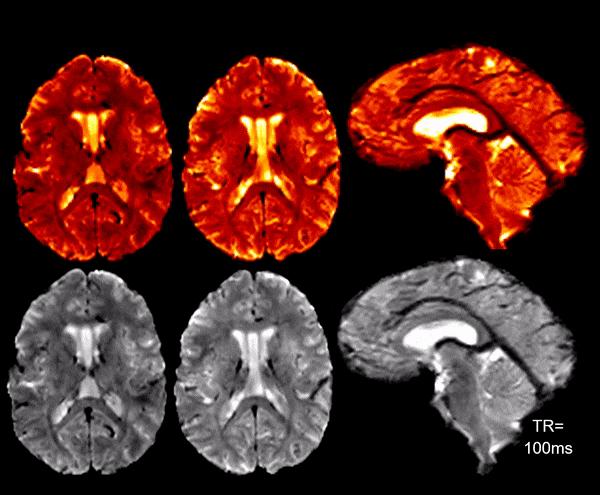

The project will support the development of the next generation Tic Tac Toe 7T MRI device, a collection of antennas that aim to image the human head and neck at unprecedented temporal and spatial resolutions. Ibrahim runs the Radiofrequency (RF) Research Facility and the 7T Bioengineering Research Program which include experimental and human studies with a whole-body 7T MRI - one of the strongest human MRI devices in the world and a powerful imaging tool that allows researchers to gain a far better understanding of brain structure and function.

Using the stronger magnetic fields in a 7T MRI along with state-of-the-art antenna and MRI technology will allow for imaging at a greater resolution, which could reveal more detailed information about pathways linking SVD and CSF flow pathophysiology to Alzheimer's disease.